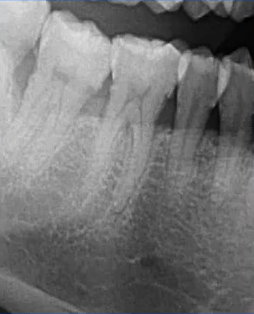

比如下面这张片子显示出的龋坏合并根尖周炎。

因为曲面断层片反映的是上下颌牙齿、上颌窦、关节,在一张片子中所展示的解剖结构较多。比如刚才的片子,最容易诊断的是右下6远中邻面深龋合并根尖周炎,左下有埋伏的多生智齿,右侧是垂直智齿。

比如对于患者右下6可以进行深龋的诊断,但是根尖炎的情况如何,或者牙根情况如何,我们需要进一步检查。比如拍摄一个根尖片或口腔CBCT,排查是否有根尖炎或根管情况。